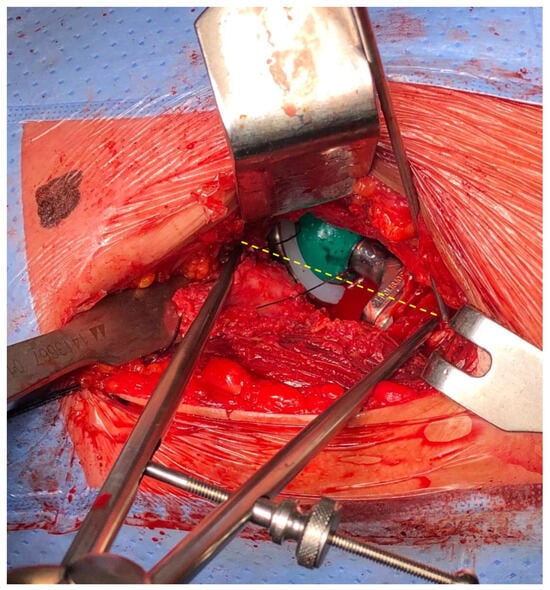

2.2. Compass Device

2.3. Surgical Technique